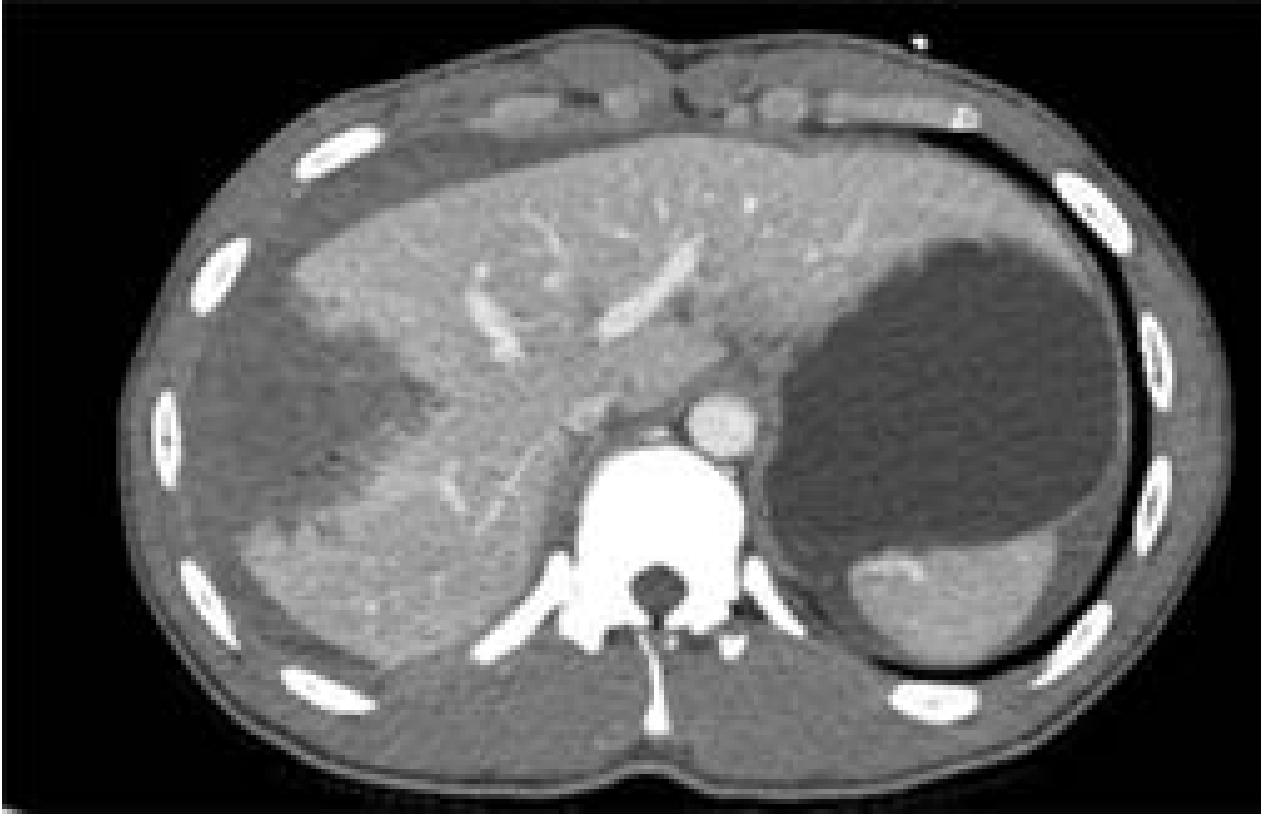

CT images of liver injury:

CT of liver injury grades

CT liver injury

CT images of liver injury — Current Surgical Therapy 14e, p. 1342

Figure — Gunshot injury to the liver successfully managed nonoperatively:

Gunshot liver NOM

Mulholland and Greenfield's Surgery, p. 1280